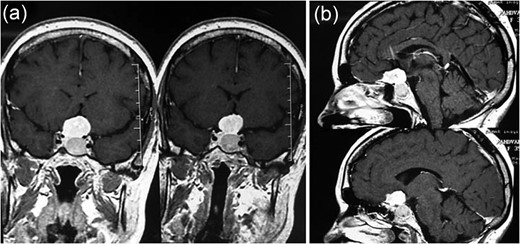

(a, b) MRI revealing a well-delineated round tumor 30 × 25 × 20 mm in diameter, T1W isointense and T2W hyperintense lesion located within the sella turcica and another dural-based lesion lying over the diaphragm sella extending to the planum sphenoidale. The intrasellar lesion showing a faint enhancement after contrast material injection but the suprasellar lesion has a bright enhancement.